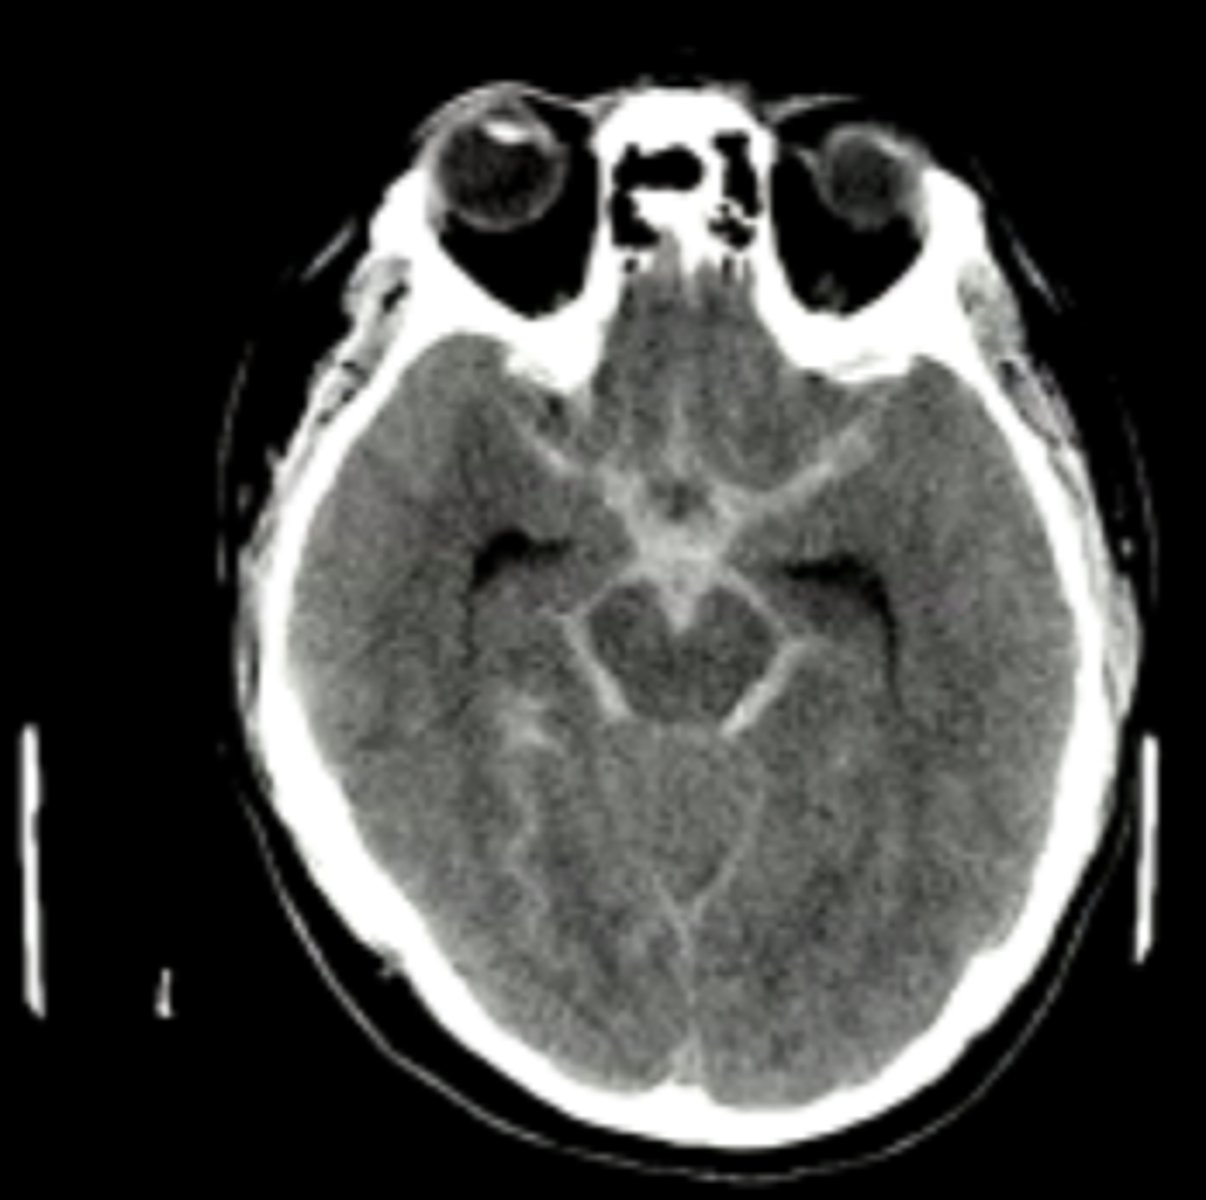

Epidural hematoma

accumulation of blood (meningeal artery) between dura and skull that is from trauma with a biconcave lens shape on CT

Subdural hematoma

accumulation of blood (bridging veins) between dura and arachnoid mater that is from acute or chronic occurrences with a crescent-shape on CT

Subarachnoid hemorrhage

bleeding between arachnoid mater and pia mater where the blood replaces the CSF and on CT it shows blood tracing down into sulci